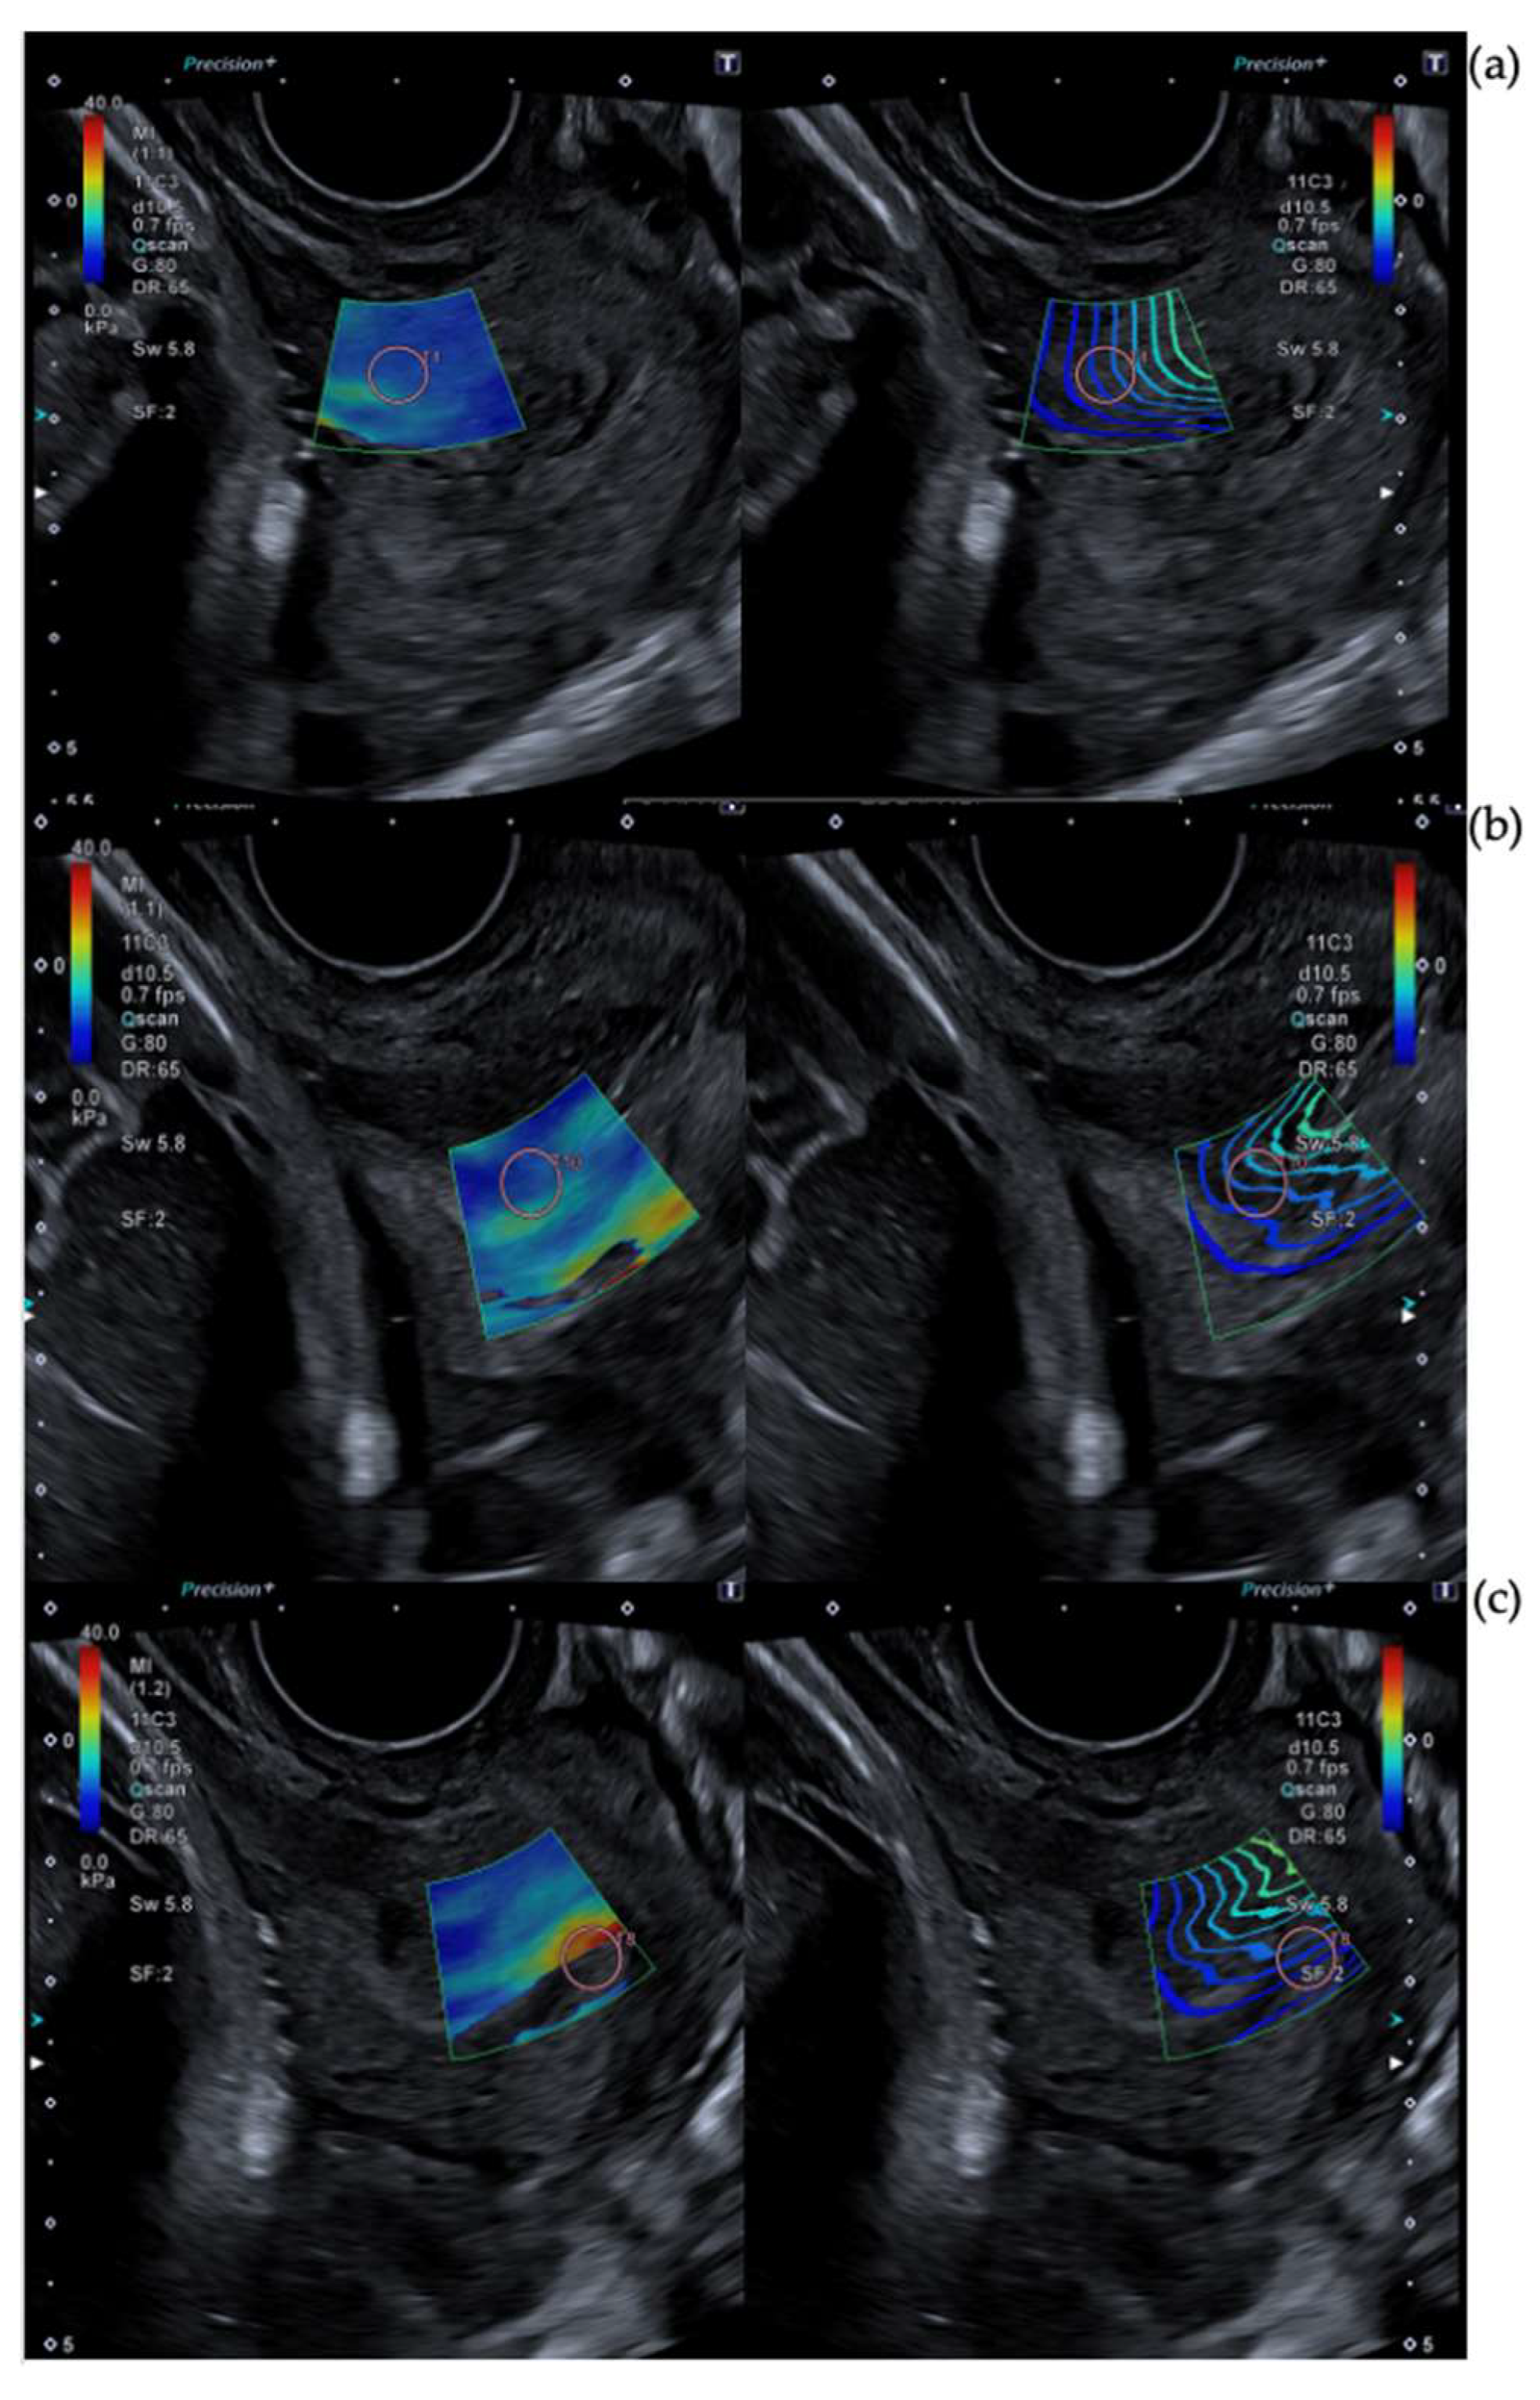

2.3. Cervical Shear Wave Elastography Measurement

- O’Hara, S.; Zelesco, M.; Sun, Z. Shear Wave Elastography on the Uterine Cervix: Technical Development for the Transvaginal Approach. J. Ultrasound Med. 2019, 38, 1049–1060. [Google Scholar] [CrossRef]

- Hernandez-Andrade, E.; Aurioles-Garibay, A.; Garcia, M.; Korzeniewski, S.J.; Schwartz, A.G.; Ahn, H.; Martinez-Varea, A.; Yeo, L.; Chaiworapongsa, T.; Hassan, S.S.; et al. Effect of depth on shear-wave elastography estimated in the internal and external cervical os during pregnancy. J. Perinat. Med. 2014, 42, 549–557. [Google Scholar] [CrossRef]